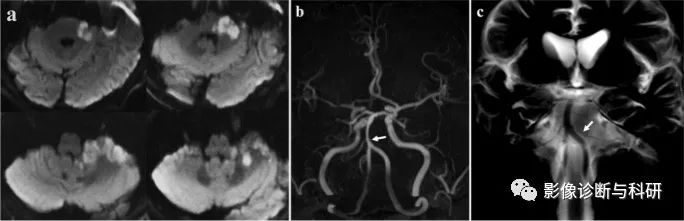

弥散加权图像显示右侧脑桥下外侧、脑桥臂和小脑上有高信号病变(a)。MRA( b),(c)显示右小脑前下动脉(AICA)未见显影